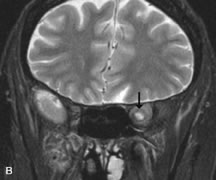

Application of a 90° RF pulse brings the excited nuclei into phase so that the net vector of their magnetic moments is directed perpendicular to the static magnetic field. Shortly thereafter, the magnetic moments of the nuclei spread out and point in different directions, leading to a loss of phase coherence and a resultant decay in signal intensity amplitude. The T2, or spin-spin relaxation time, is the rate of decrease in the signal of these excited nuclei as a result of the interaction and transfer of energy to unexcited adjacent nuclei. T2 ranges from a few milliseconds to a few hundred milliseconds and, for a given tissue, is always less than the Tl relaxation time. T2-weighted orbital images are easily recognized by a high-intensity signal from the vitreous (Fig. 9).5,8,16